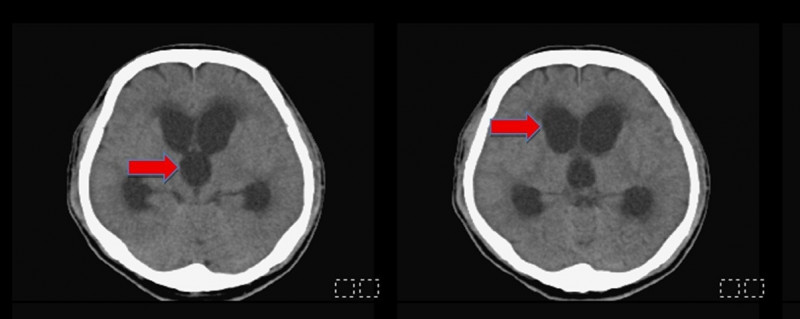

〔記者許麗娟/高雄報導〕48歲油漆工工作不慎撞到頭,導致頭部外傷、顱內出血,就醫後接受保守治療未開刀,但某日突然出現意識不清、嗜睡送到醫院急診,腦部電腦斷層檢查發現腦室腫大為水腦症,經緊急手術引流腦脊髓液,術後已恢復意識、改善行動力,亦已重返工作崗位。

該名油漆工頭部受傷後未手術,採保守治療,家屬因照顧問題送至安養機構入住,因意識不清、嗜睡送來急診時,因腦室明顯腫大,緊急進行「腦室腹腔分流手術」,於腦室置放引流裝置並連接至腹膜腔,將蓄積多餘的腦脊髓液排出,患者病症大幅改善。

陳志豪強調,早期辨識與介入治療是改善預後的關鍵,臨床可透過電腦斷層(CT)或磁振造影(MRI)影像學判斷及病程追蹤來評估是否需進行分流手術。此個案是手術後才恢復清楚意識及記憶,術後半年追蹤,原先腫大的腦室已恢復正常大小,並已恢復如常的生活。